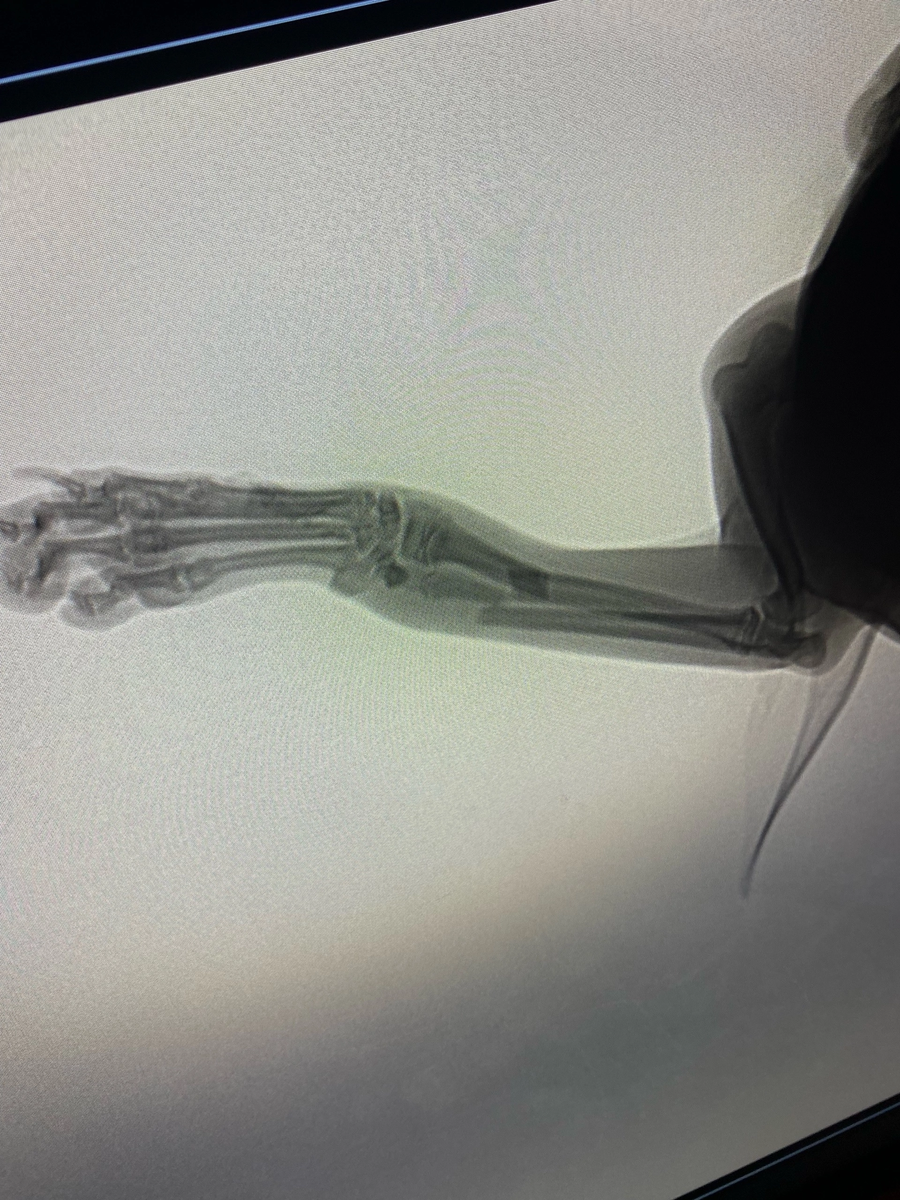

На следующий день мы приехали в клинику нам сделали рентген и сказали что у песика перелом со смещением.

Я согласился на операцию сказали что будут резать лапку вставлять болты и 2 спицы , за такую операцию запросили 26 000 рублей .